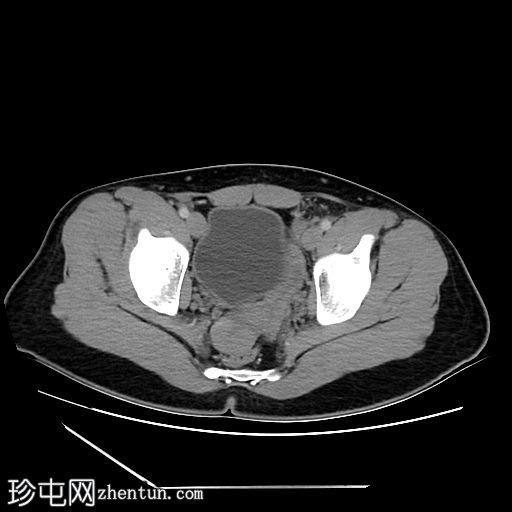

轴位增强扫描

门静脉期

阴茎:发育良好。阴茎海绵体和尿道海绵体均存在。

阴囊:双侧均存在,但空虚。

盆腔左侧可见一形态良好的子宫样结构(57 x 17毫米),开口于前列腺尿道。

右侧睾丸位于盆腔右侧,膀胱与直肠之间。大小:56 x 29 毫米。

左侧睾丸位于盆腔中线左侧,膀胱上方,子宫底旁。该结构附着于从左侧腹股沟管延伸出的索状结构上。大小:38 x 22 毫米。

患者有双侧隐睾病史。CT和MRI图像显示发育良好的子宫和两个睾丸,均位于盆腔内。子宫内膜腔开口于前列腺尿道。

该患者表型为男性,阴茎发育良好。精液分析显示无精子症。结合影像学检查结果,最可能的诊断是持续性苗勒氏管综合征。这是一种男性假两性畸形,由子宫内抗苗勒氏管激素(AMH)分泌不足引起。AMH或其信号通路的缺乏导致苗勒氏管衍生结构的持续发育。